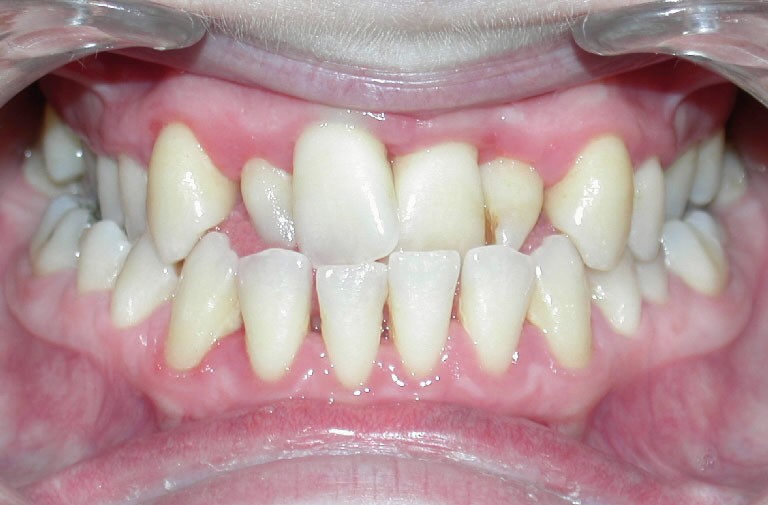

Cette patiente est venue consulter pour son occlusion inversée et ses importantes malpositions dentaires antérieures associées à la perte d’une dent et à des problèmes parodontaux.

Le sourire est inesthétique (fig. 3) et de profil il existe une rétrochéilie supérieure (fig. 2).

Sur le plan parodontal, il existe une gingivite résiduelle à une gingivectomie (la patiente étant sous anti-épileptiques).